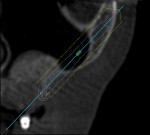

Pretreatment planning with planning software (NobelClinician, Nobel Biocare) was accomplished prior to zygomatic surgical protocols (Figure 10). Figure 11 demonstrates the sagittal view of the presurgical treatment planning processes and the volume of the patient's right zygomatic arch, along with the planned positioning of the 45 mm zygomatic implant spatially to deliver the coronal aspect of the implant in the correct position of the arch to minimize prosthetic thickness of the interim definitive prosthesis. The patient was scheduled for maxillary revision surgery and placement of single zygomatic implants bilaterally, with evaluation of the remaining implants for either continued use or removal.